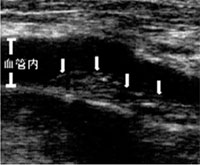

エコー 写真  具体的に、この検査でどういったことがわかるのかあげてみます。

まず頚動脈エコー検査では、頚部を上行する頚動脈の動脈硬化の程度を目で見て評価することができます(写真)。

超音波検査は、この動脈硬化を目で見て評価をすることができます。さらに頚動脈エコーでの動脈硬化の評価は、全身の動脈硬化の指標ともなります。

IMTは加齢により増加しますが、健常人では高齢者でも1.1mmを超えることはありません。